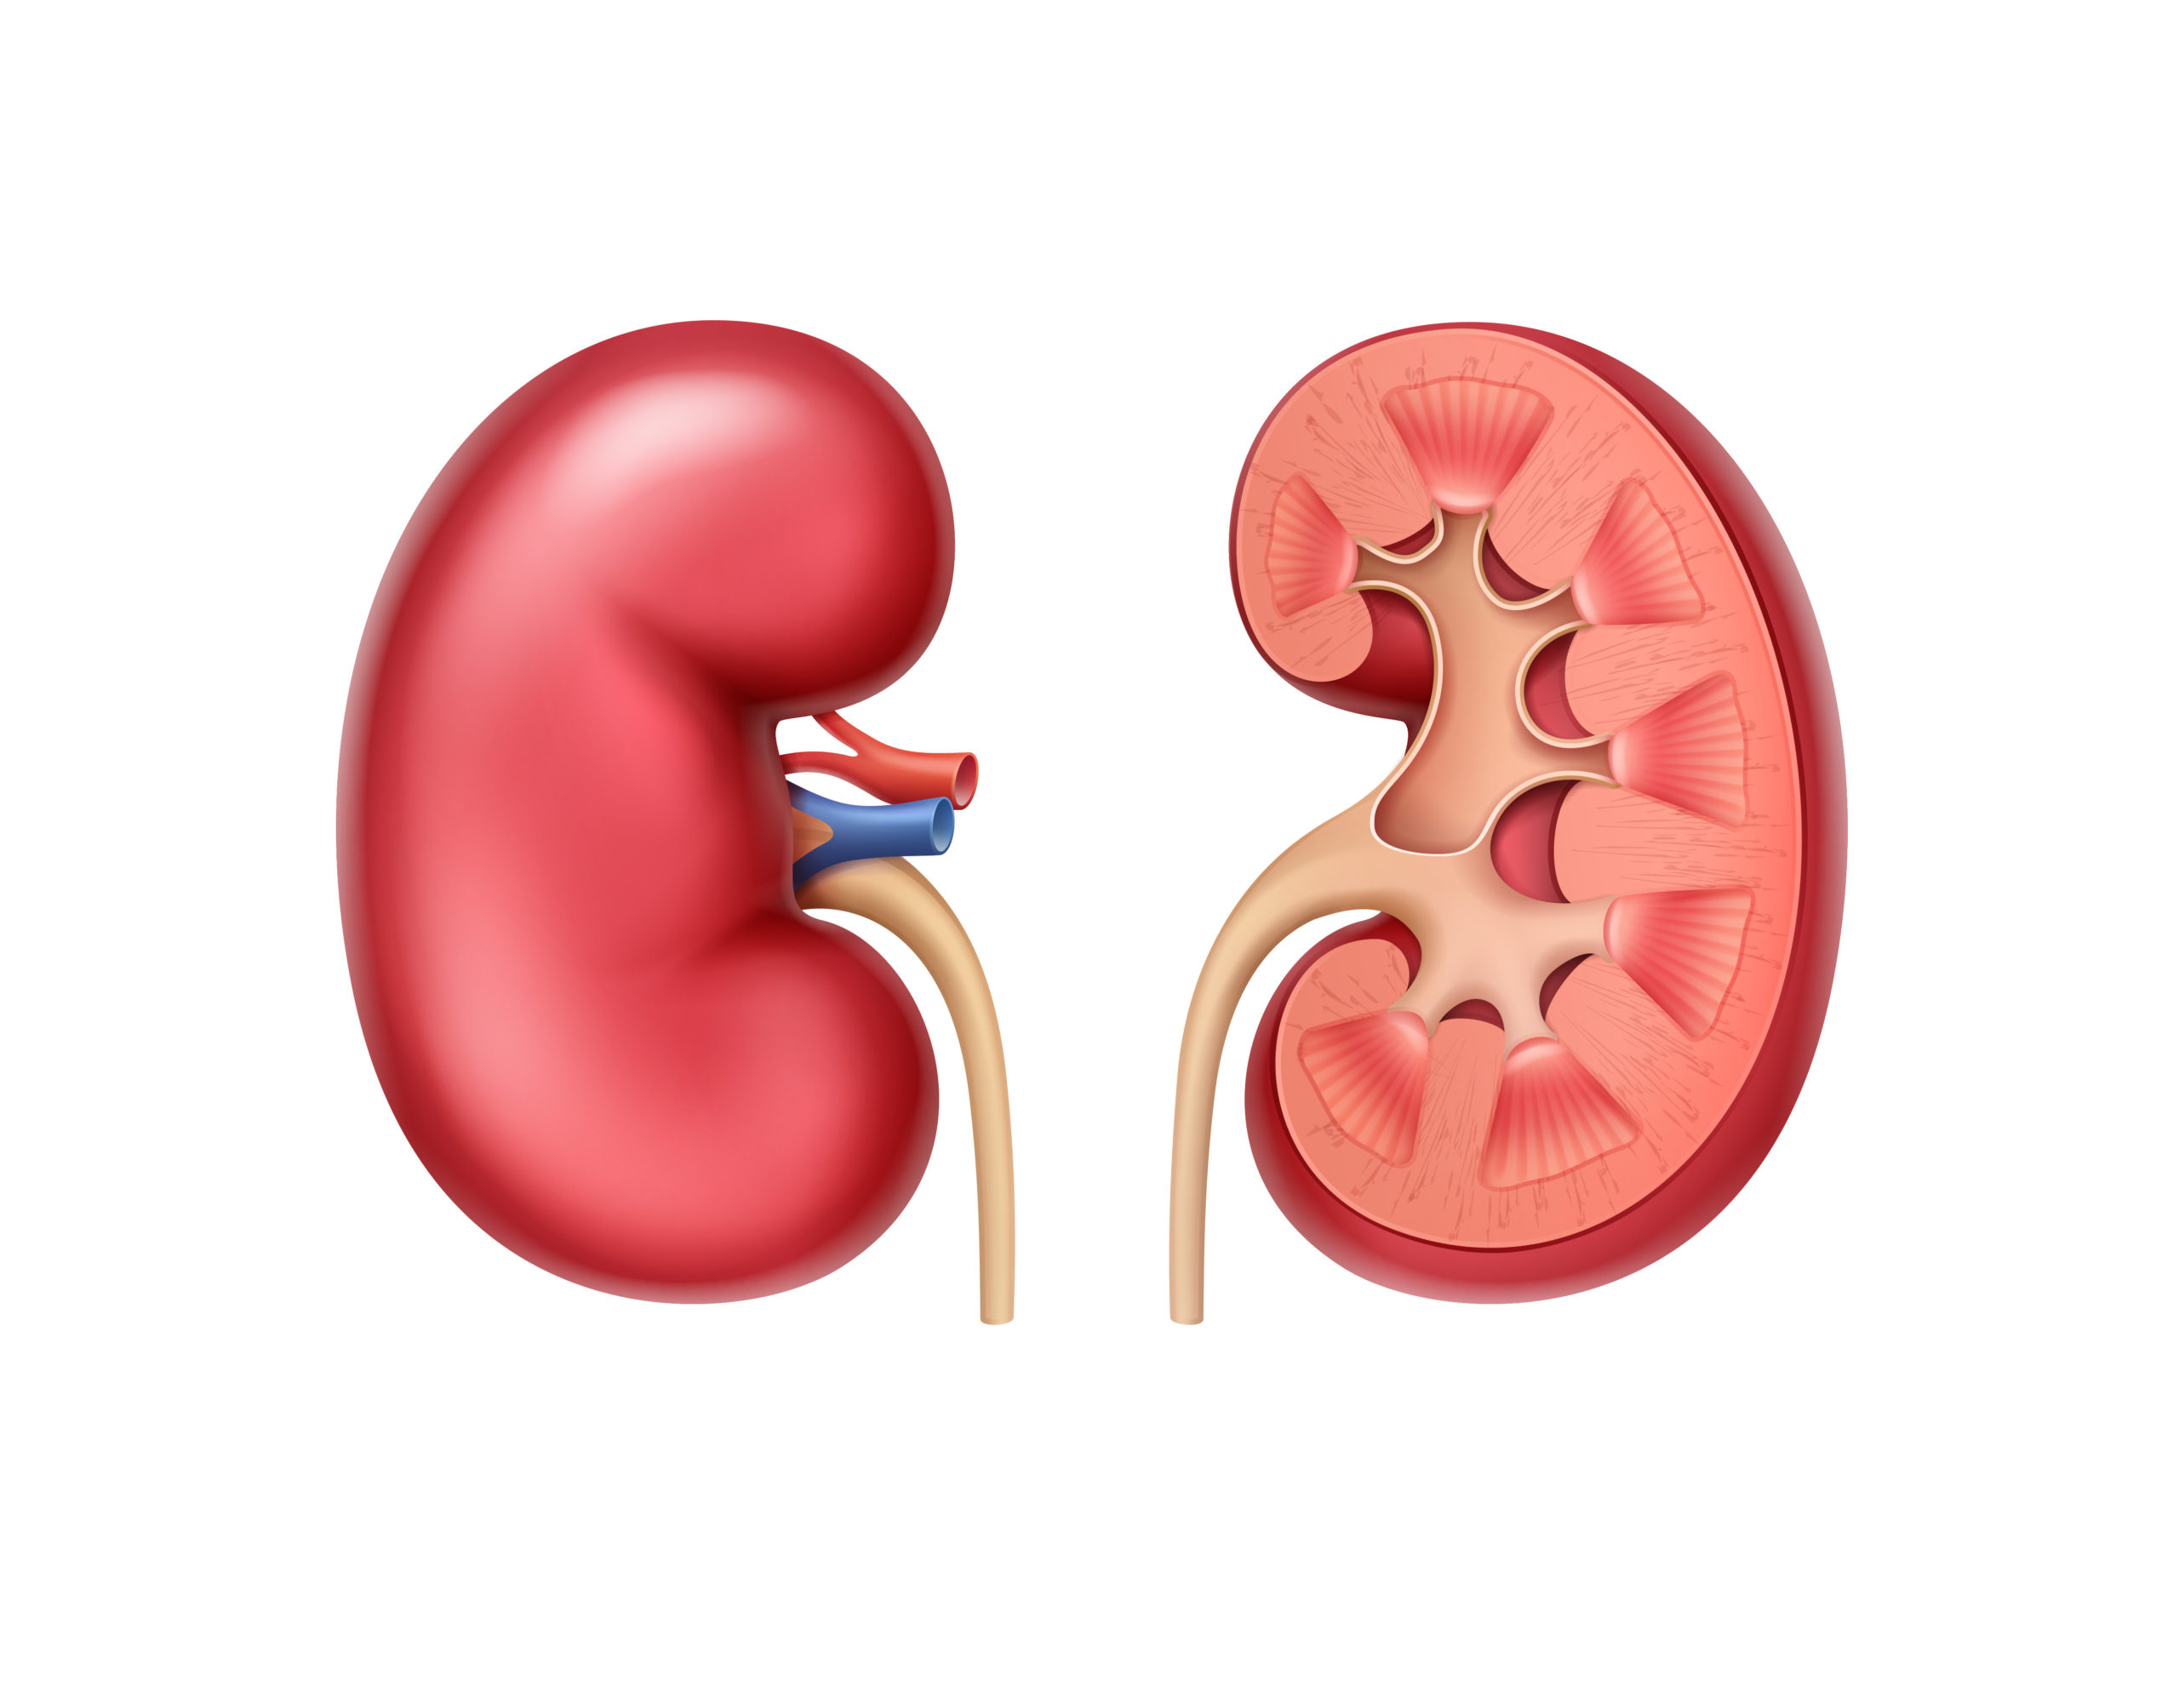

kidney function